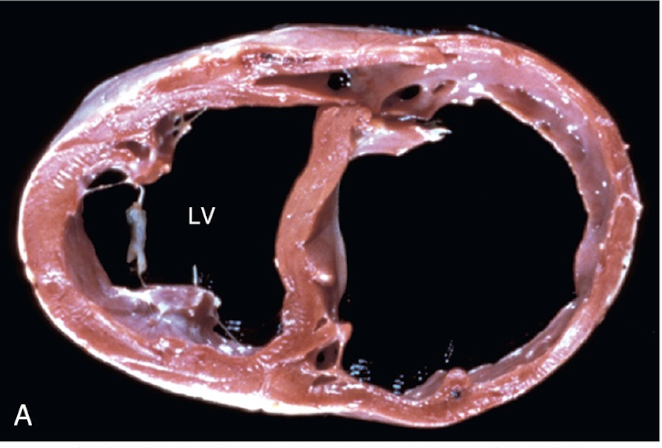

22

Q

ID + pathogenesis

A

Dilated Cardiomyopathy – dogs

- 1º systolic dysfunction that leads to 2º dilation